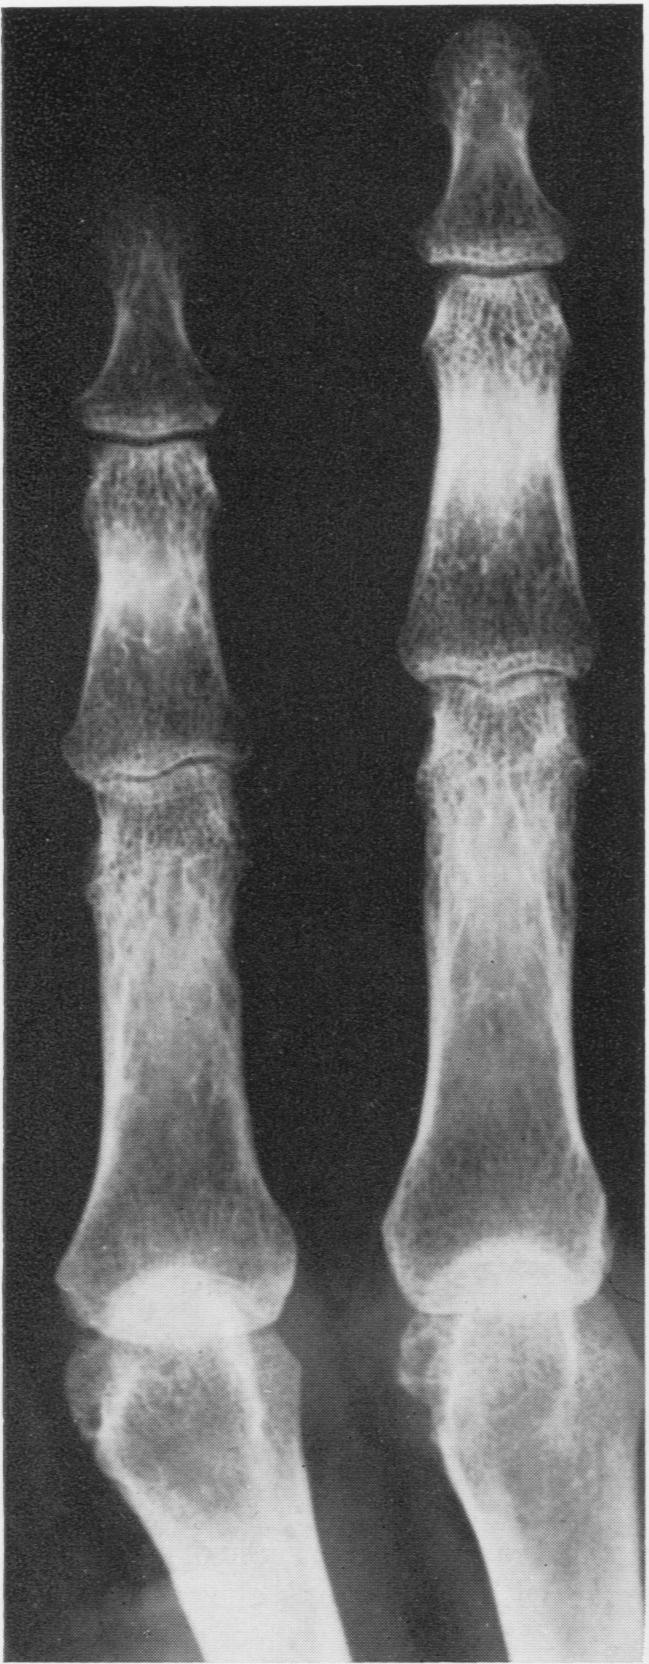

Honeycomb lung and chronic rheumatoid arthritis; a case report.

Ann Rheum Dis. 1957 Jun;16(2):241-5. doi: 10.1136/ard.16.2.241.